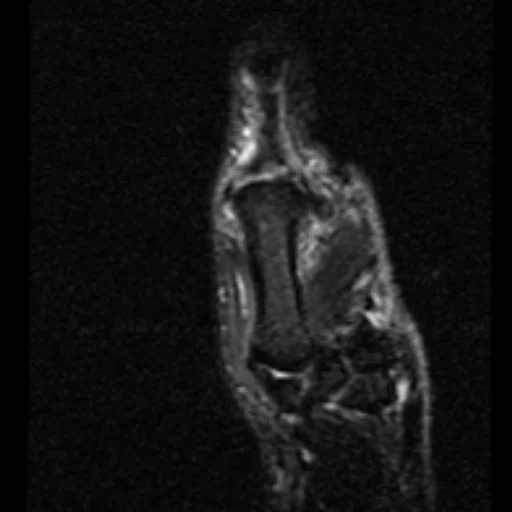

Stener Lesion

• Torn UCL (gamekeeper thumb) results in adductor pollicis aponeurosis/muscle pushing itself between the MCP joint and the UCL

• Prevents healing so need surgery

• Yo-yo on a string

• Case courtesy of Roberto Schubert, Radiopaedia.org, rID: 16731 (stener lesion)